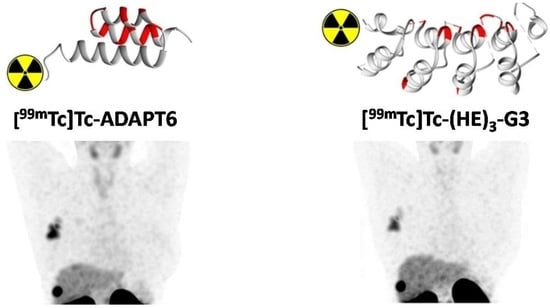

Direct Intra-Patient Comparison of Scaffold Protein-Based Tracers, [99mTc]Tc-ADAPT6 and [99mTc]Tc-(HE)3-G3, for Imaging of HER2-Positive Breast Cancer

1. Introduction

2.3. Radiochemistry